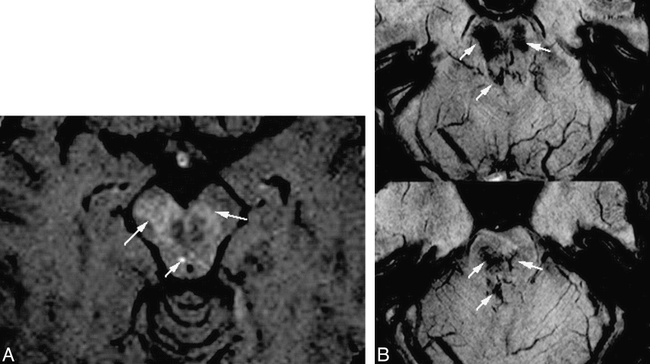

Comparison of HRBV and contrast-enhanced T1-weighted images.

A, Contrast-enhanced T1-weighted image (750/20 [TR/TE] with one acquisition) shows slight enhancement (arrows).

B, HRBV image shows abnormal vessels in the same regions compatible with telangiectasias. Some of the vessels have configurations of veins.